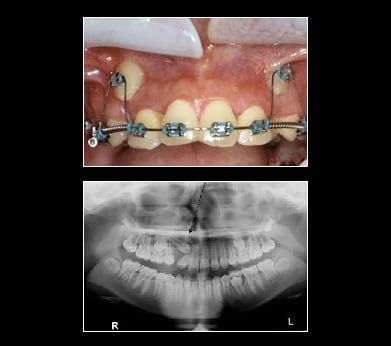

Treatment for Impacted Canines

After assessing your situation, InfoStar Dental Template 3 will devise a plan to make room for your canines. With a typical oral surgery and the assistance of an orthodontist your canine will find their way into their proper place over time.